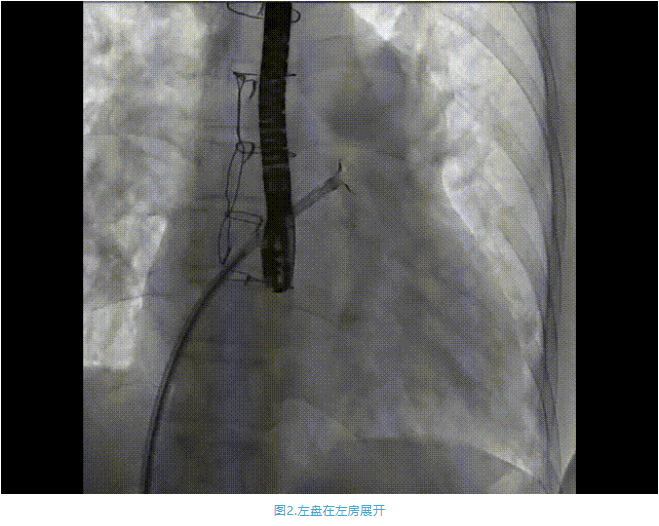

術(shù)中首先在局麻下穿刺股動(dòng)脈、股靜脈,完成心導(dǎo)管檢查評估后轉(zhuǎn)為全麻,在食道超聲引導(dǎo)下穿刺房間隔,穿刺成功后將加硬導(dǎo)絲送入左上肺靜脈建立軌道,根據(jù)患者病情行球囊預(yù)擴(kuò)張后植入6mm孔徑房間隔造孔支架,經(jīng)透視及食道超聲評估支架左右盤展開良好,夾持于房間隔兩側(cè),固定穩(wěn)定、位置良好,食道彩超顯示房水平右向左為主分流,分流孔直徑符合預(yù)期大小,心導(dǎo)管檢查評估達(dá)到預(yù)期效果,釋放造孔支架。術(shù)后12h患者下床活動(dòng),恢復(fù)順利,擬于近日完善術(shù)后評估后出院。